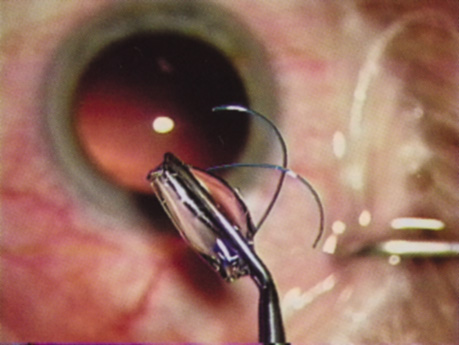

INTRAOCULAR LENS IMPLANTATION

Intraocular lens pioneers such as Cornelius Binkhorst, Peter Choyce, Jan Worst, Edward Epstein, Steven Shearing, and Svyatoslav Fyodorov among many others modified IOL design and the location for implantation. In England, John Pearce returned the IOL to the posterior chamber preceding the development of the Shearing style lens, which marked the real acceptance of the IOL. The safety and growing popularity of intraocular lenses was intimately linked to the introduction of Healon, a hyaluronic acid derived from Swedish rooster combs. It was Pape and Balaz who pioneered the concept of viscosurgery in 1979.12 Modern implant surgery was revolutionized by Richard Kratz, Robert Sinskey, William Simcoe, John Sheets, Norman Jaffe, Gerald Tennant, Eric Arnott, and Charles Kelman. Outstanding teachers such as David McIntyre, Jared Emery, Henry Hirschman, Herve Byron, Richard Lindstrom, Harry Grabow, Douglas Koch, Roger Steinert, and Samuel Masket spread the word as phacoemulsification techniques, improved instrumentation, and IOL designs proliferated.

Another huge step forward was taken in the early 1980s when French surgeon Danielle Aron-Rosa and her colleagues introduced the neodymium:yttrium-aluminum-garnet (Nd:YAG) laser for performing posterior capsulotomy, which eliminated an additional procedure in the operating room.13 Clifford Terry introduced the surgical keratotomer, which provided us with a new understanding of astigmatism,14 leading to the combination of astigmatic keratotomy with phacoemulsification to reduce pre-existing astigmatism introduced by Robert Osher in 1983.15,16 Then in 1985, Thomas Mazzocco developed and implanted the first foldable IOL17; Australian Graham Barrett and associates ushered us into the materials era with the use of silicone, hydrogels, and acrylics.18 Remarkable insights by David Apple correlated clinical observation with histopathology using the photographic technique developed by Kensaku Miyake of Japan.19

Refractive lens replacement and phakic implantation also were gradually earning a rightful place in anterior segment surgery. In the early 1980s, Franco Verzella from Italy initially removed the clear lens for extreme myopia, but surgeons were concerned about the incidence of retinal detachment in this group of high-risk eyes. Robert Osher performed the first clear lensectomy for hyperopia in 1985 and although the risk of retinal detachment was lower, these eyes were challenging both in surgery and in accurately selecting the IOL.34,35 John Gayton's novel approach of using “piggyback” IOLs met with enthusiasm until interlenticular opacification emerged.36 AcriTec engineers from Germany identified a method of manufacturing lens power up to +60 diopters. Phakic implantation with IOLs fixated in the anterior chamber (Baikoff, Kelman, Choyce) and the posterior chamber (Fyodorov, Adatomed, PRL, Staar Surgical) were being developed. The iris-supported Verisyse (Artisan developed by Jan Worst) became the first phakic IOL approved in the United States.